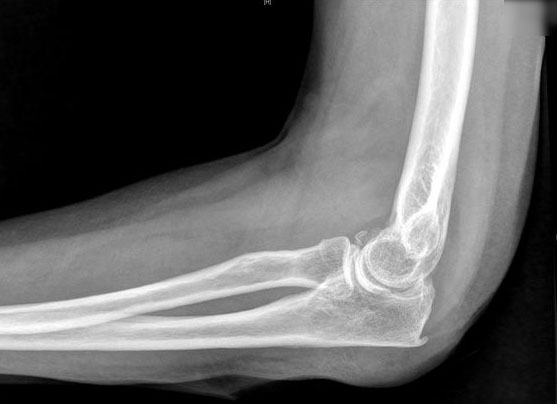

Fractura supracondílea de codo.

Fractura supracondílea de codo.Tras reducción y osteosíntesis.

Fractura supracondílea de codo. Tratamiento con agujas.